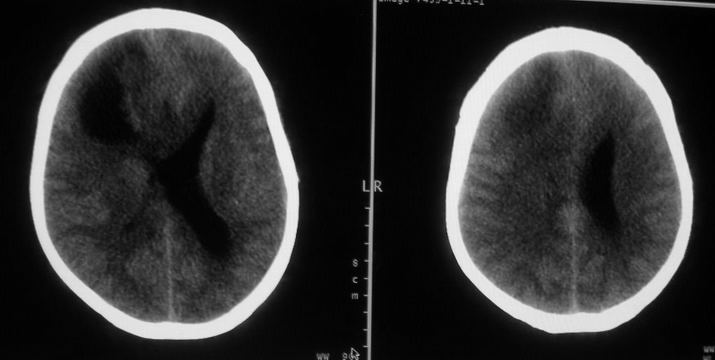

女,44岁,头痛数月。

右侧额叶占位性病变,考虑脑肿瘤;建议行进一步检查。

右侧额叶占位性病变,考虑脑膜瘤可能性大;建议行进一步检查。

囊性脑膜瘤